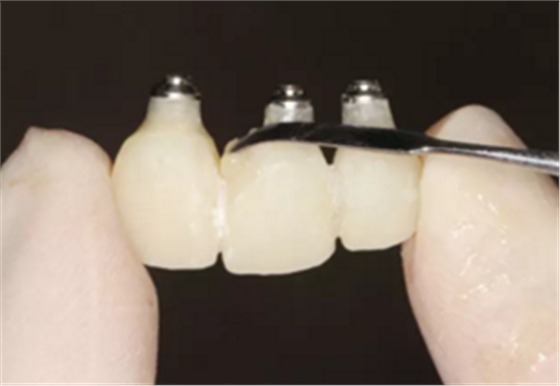

(4)最终修复。种植体周围软组织改建成熟以后,进行最终修复。本 病例采用两步法印模技术精确记录种植体的三维位置和种植体周围软组织穿 龈轮廓外形。 首先,口内制取临时冠及周围软硬组织的硅橡胶阴模,复制软硬组织 表面形态。然后,取下临时修复体,常规制取闭窗式种植体水平聚醚印模, 精确记录种植体的三维位置,灌制含人工牙龈的超硬石膏模型。最后,去除 模型上的人工牙龈,将临时修复体戴入到模型上,在临时修复体周围和硅橡 胶阴模内注入人工牙龈,将阴模就位到含临时冠的石膏模型上,精确转移穿龈轮廓外形,获得工作模型。 制作螺丝固位的一体化氧化锆基台冠,以切削方式制作完成后,表面 添加饰瓷来获得理想的美观效果。 术后7个月,戴入最终修复体,红白美学效果满意。

图22 最终修复体

图23 最终修复后即刻口内像